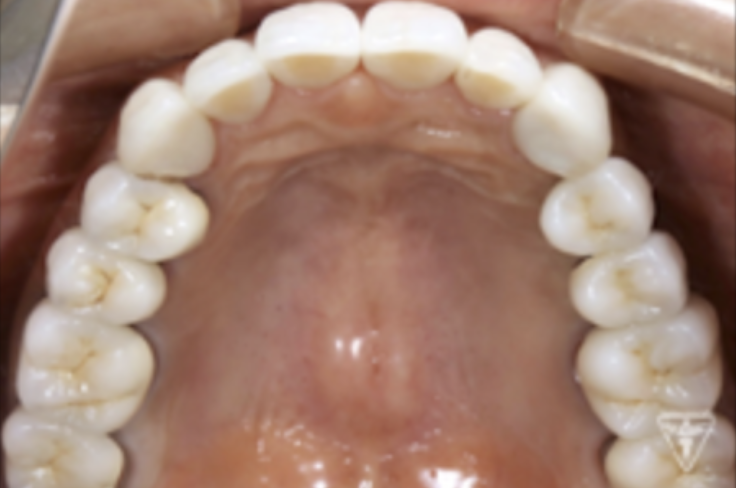

最終補綴物装着時

咬合平面の評価(SHILLAⅡの平面板による)

治療後